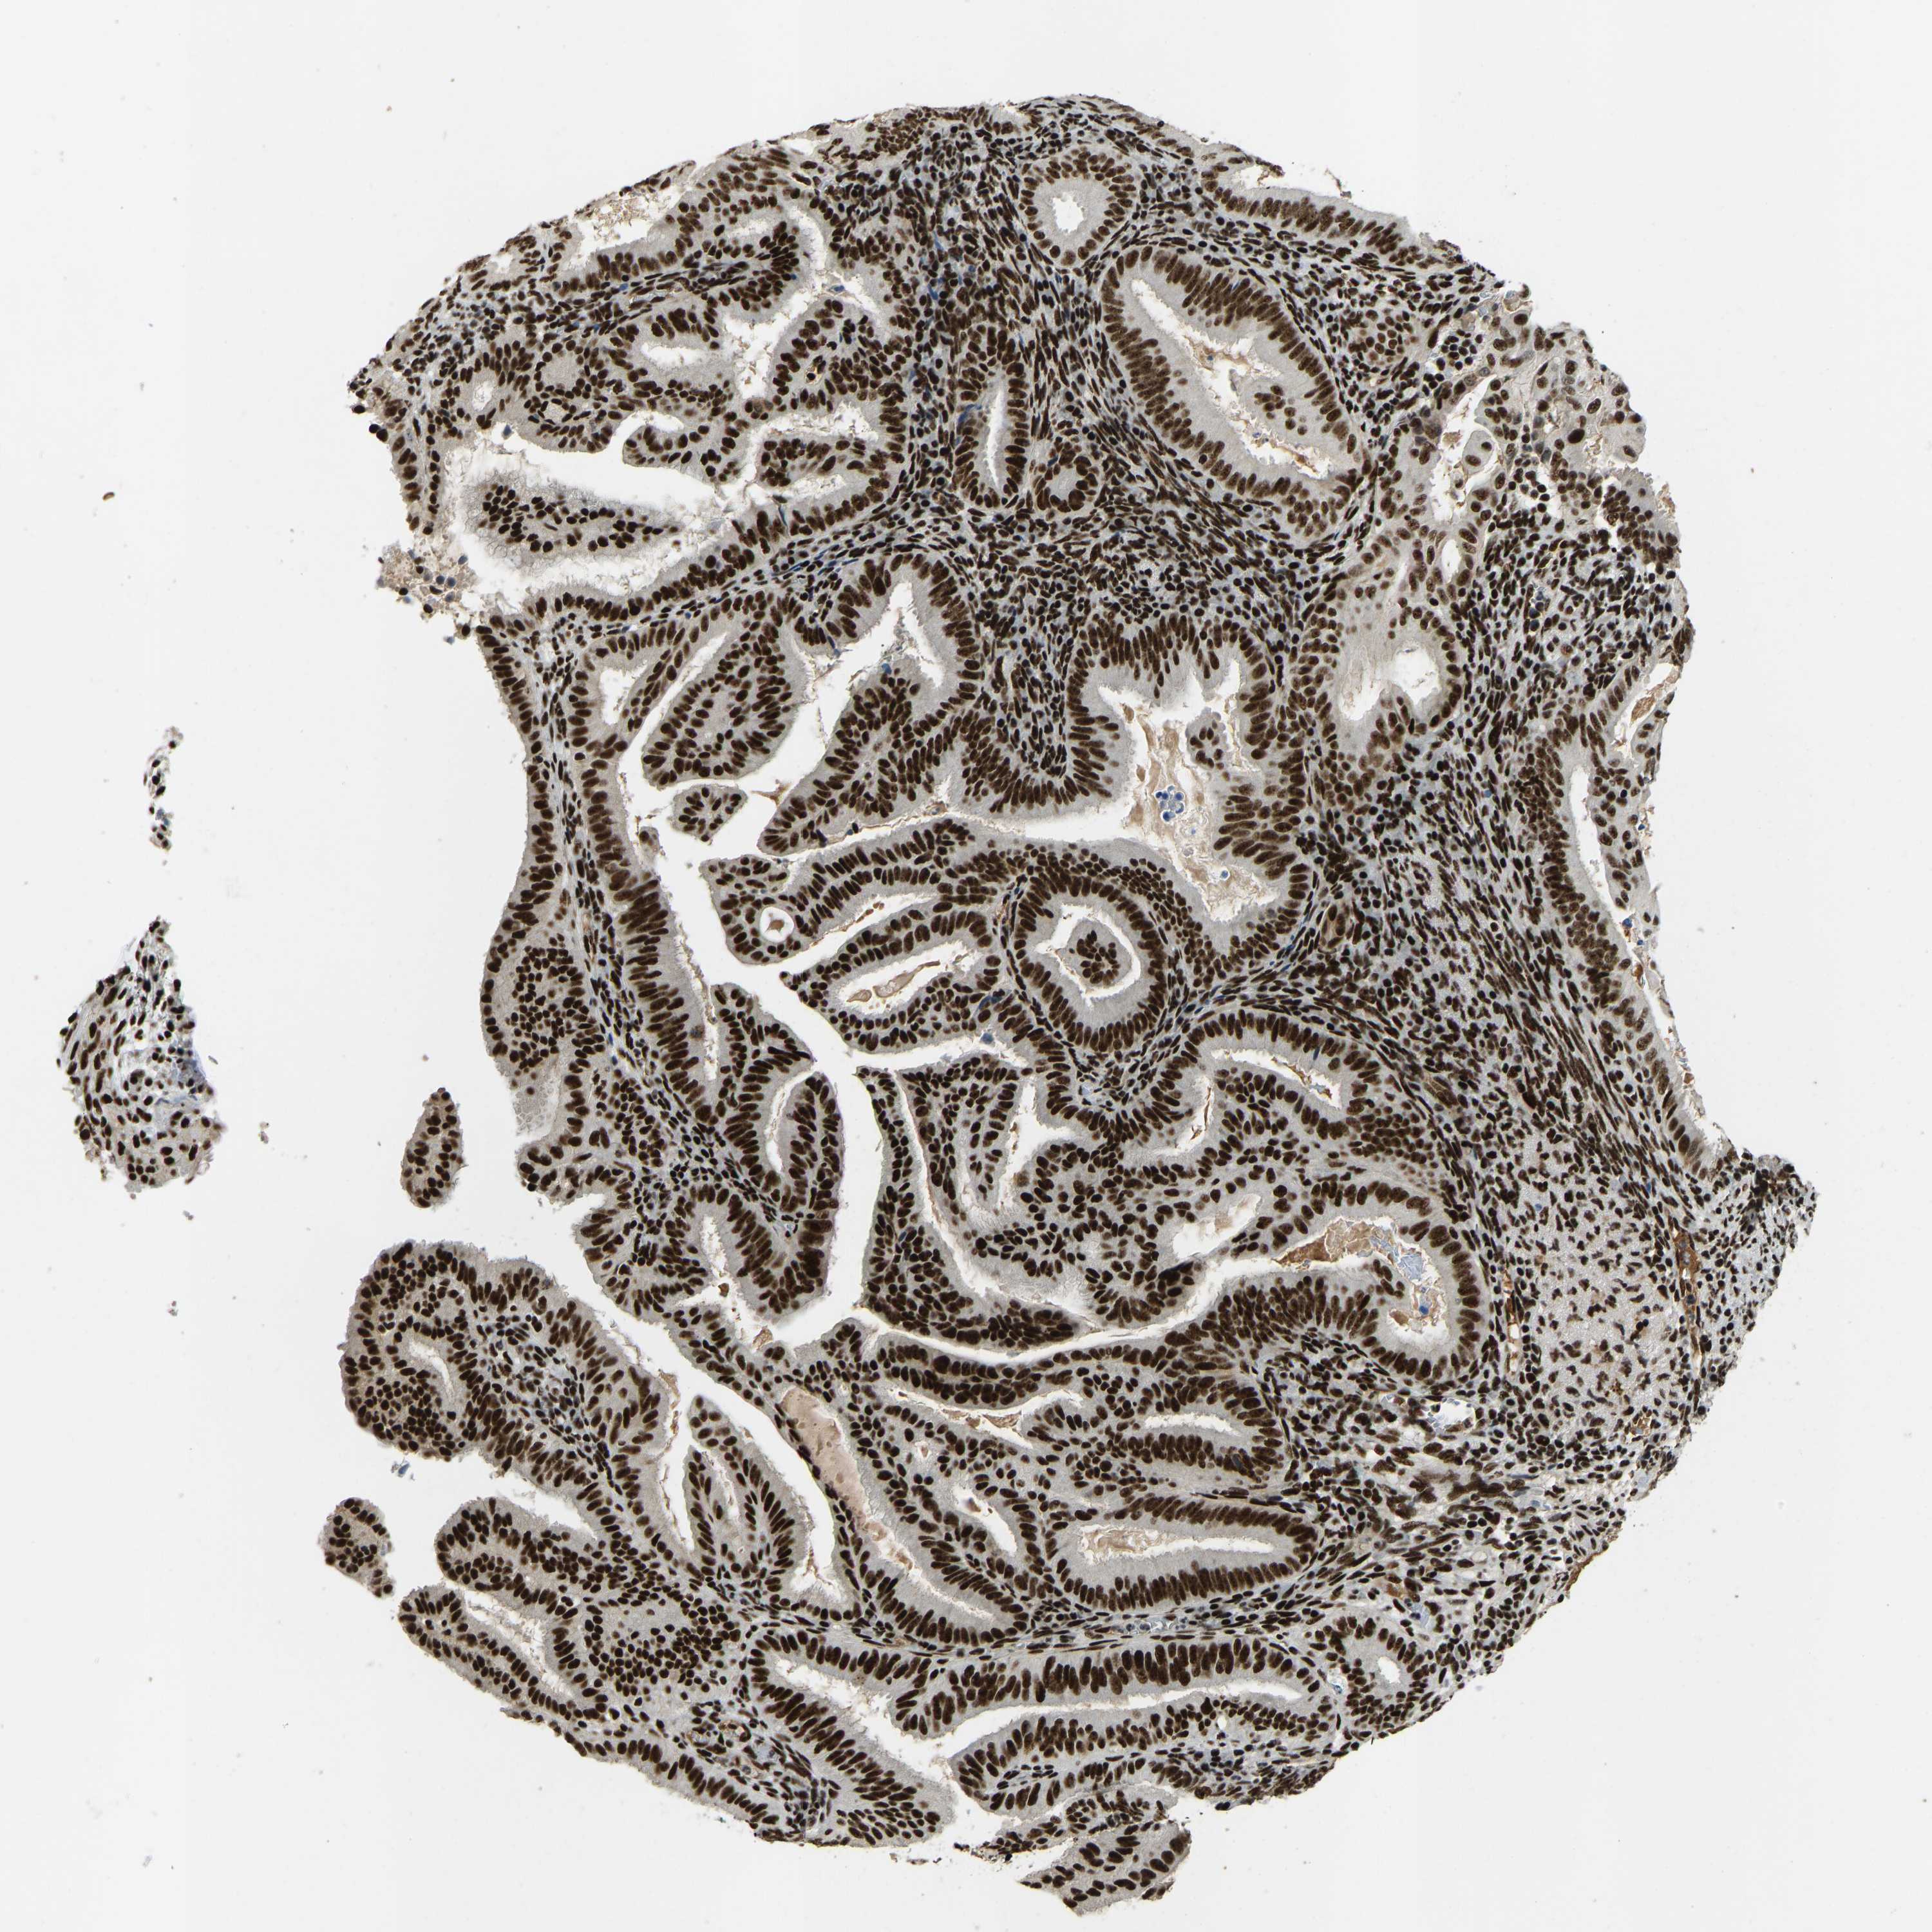

ENDOMETRIAL CANCER - Protein expressioni

A mouse-over function shows sample information and annotation data. Click on an image to view it in a full screen mode. Samples can be filtered based on level of antibody staining by selecting one or several of the following categories: high, medium, low and not detected. The assay and annotation is described here.

Note that samples used for immunohistochemistry by the Human Protein Atlas do not correspond to samples in the TCGA dataset.

Antibody stainingi

Antibody staining in the annotated cell types in the current human tissue is reported as not detected, low, medium, or high, based on conventional immunohistochemistry profiling in selected tissues. This score is based on the combination of the staining intensity and fraction of stained cells.

Each image is clickable and will lead to virtual microscopy that enables deeper exploration of all samples and also displays staining intensity scores, fraction scores and subcellular localization as well as patient and tissue information for each sample.

Antibody HPA017998

Antibody HPA018864

Staining

High

Medium

Low

Not detected

Intensity

Strong

Moderate

Weak

Negative

Quantity

>75%

75%-25%

<25%

None

Location

Nuclear

Cytoplasmic/membranous

Cytoplasmic/membranous,nuclear

Adenocarcinoma, NOS